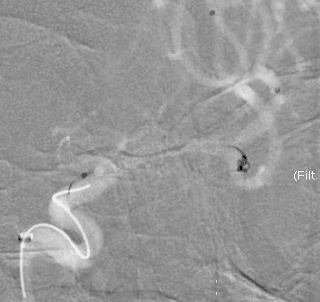

术前影像

栓塞过程

Presgo®微导丝引导支架微导管于基底动脉末端,并预留支架。陆续填塞Jasper®SS弹簧圈4枚,瘤腔填塞致密,撤出支架系统。

术后即刻影像